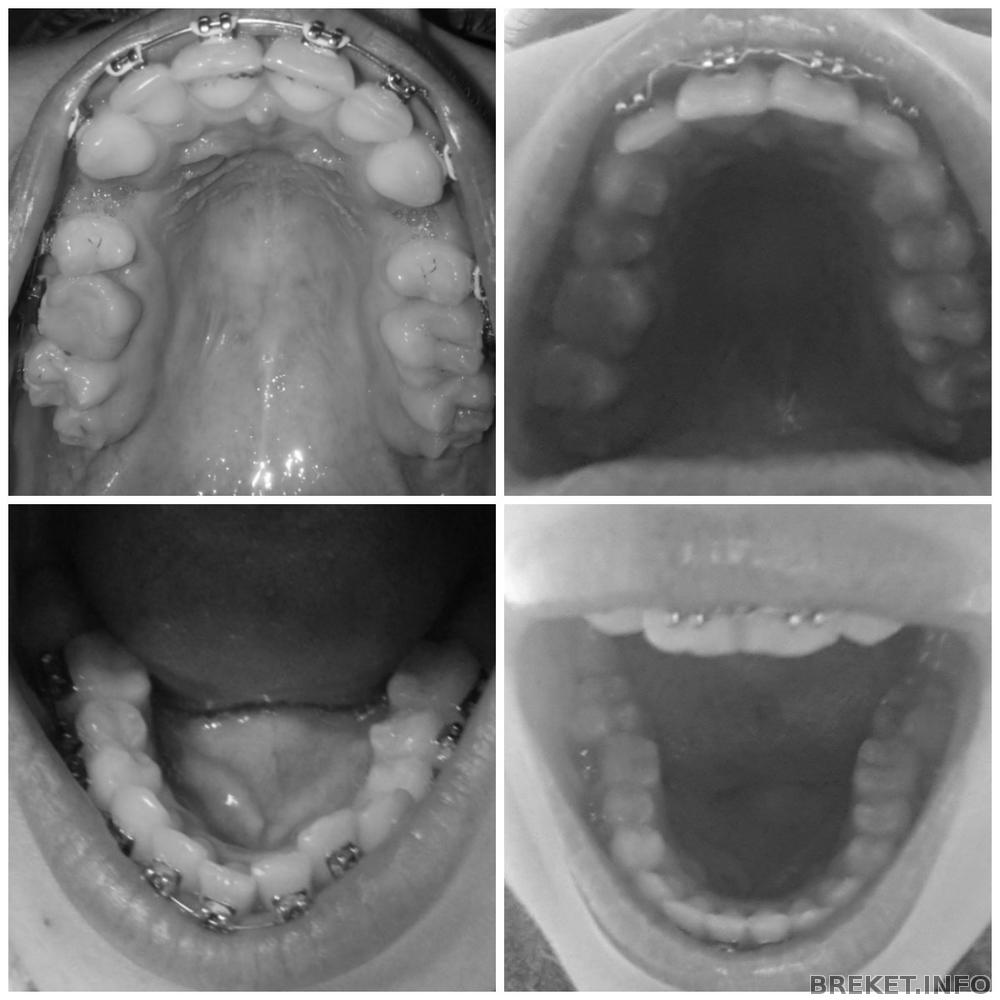

RaiseHopes, Да, уж.., посмотрела я на вашу нижнюю челюсть. У вас тоже беда. Такое ощущение будто челюсть узкая, а потом БАЦ и семерки широко стоят. Вот не хочу я такого. Мне мой орт тоже сказала, ну если я ооооочень хочу, то она мне поставит, но я буду жалеть, если подключу семерки, что это болезненное все и чистить проблематично. Но такая картина как у вас, меня бы точно не устроила.

Varechka, в идеале, как я себе представляла, что 6ки все-таки должны стоять ровно. Вот даже посмотреть на продемонстрированном коллаже от RaiseHopes. Там с семерками беда, но шестерки внизу хорошо стоят. А у меня вообще нет ровной "подковы". Про центр - конечно, если ровнять верх, то и низ, так как они в тандеме.

shelkovaya01@mail.ru, у вас еще все более-менее) думала, что катастрофа, а как фото посмотрела- не так уж и плохо. У меня с этим вообще беда. Шестерки на НЧ очень съехали внутрь, семерки на ВЧ развернуты в сторону щек так, что они мне реально мешают. Спрашивала орта нормально ли это, т.к. брекеты тоже до шестерок стоят, он сказал - конечно не нормально. Правда потом пару раз пришлось напоминать. Договорились с ним: я удаляю все восьмерки и начинаем доклеивать замки на 7ые. Решили снизу начнем. Но вышло по-другому, он посмотрел и начал с ВЧ. Час клеил, еле-еле, постоянно замки срывались, настолько сильно семерки развернуты. Дугу вставлял- опять слетали. С горем пополам таки приклеил замки на 7ки) поставил дугу слабее, чтоб опять не отпали, еле выгнул ее как надо. Вообщем, очень сложно было. Но все возможно))